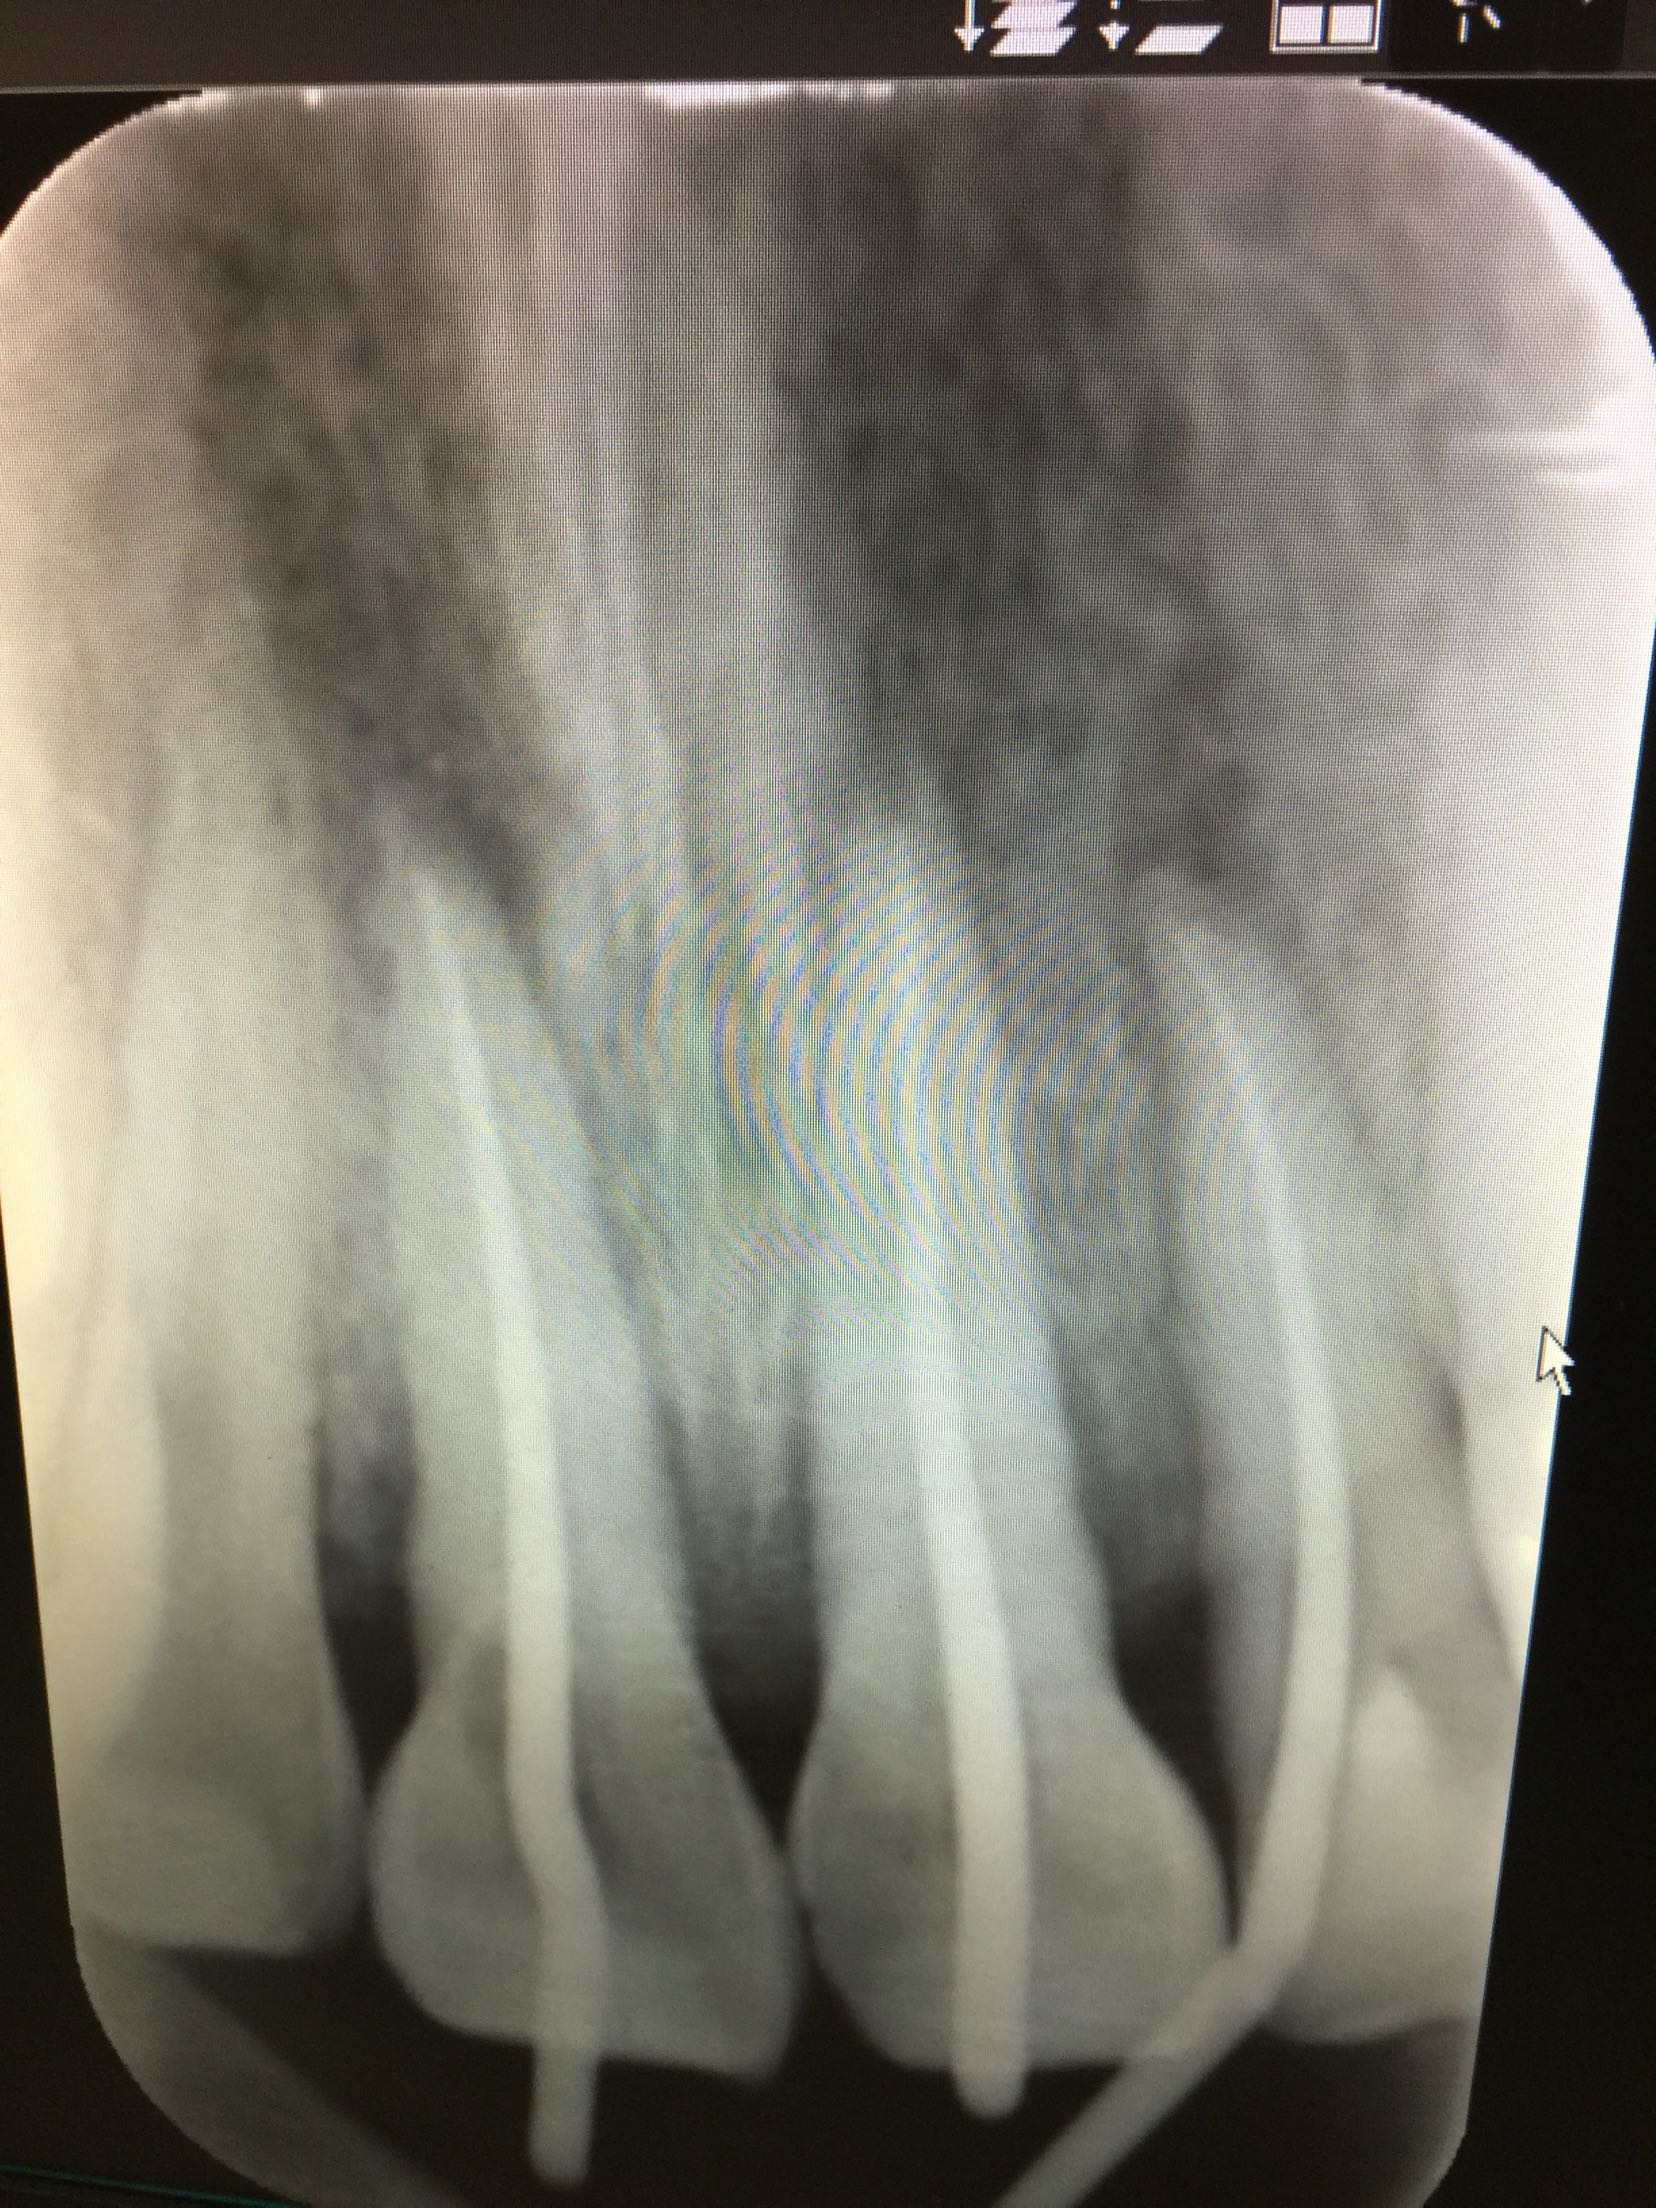

检查:11,21牙舌侧移位,不松,22牙腭侧折裂至龈下,折裂片松动III度,叩+,咬合关系紊乱。 检查:ct示11.21牙脱位伴牙槽骨骨折,22牙腭侧折裂位于牙槽脊顶下。

诊断:11牙21牙侧向移位 22牙复杂冠根折 上颌骨骨折 治疗计划:11,21牙请颌外会诊 22牙拔除折裂片后试情况制定下一步治疗计划。 请颌外会诊上颌骨骨折 治疗:患者于外科行上颌骨骨折固定求及拔除22牙折裂片后行13-23松牙固定术后。来我科行11.21.22牙根管治疗术。开髓后清扩,消毒,封veta-pex。两周后复诊。 复诊,诊间无不适。试主尖